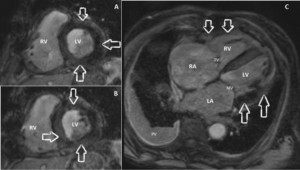

Figuur 3 a,b,c: MRI beelden met delayed enhancement

a. MRI beeld delayed enhancement. Korte as opname. Let op de uitgebreide afwijkingen in de wand van zowel de linker- als rechterventrikel (witte pijlen): transmuraal “patchy” delayed enhancement. LV = linkerventrikel. RV = rechterventrikel.

b. MRI beeld delayed enhancement. Korte as opname. Let op de uitgebreide afwijkingen in de wand van zowel de linker- als rechterventrikel (witte pijlen): transmuraal “patchy” delayed enhancement. LV = linkerventrikel. RV = rechterventrikel.

c. MRI beeld delayed enhancement. 4-kamer opname. Let op de uitgebreide afwijkingen in de wand van zowel de linker- als rechterventrikel (witte pijlen): transmuraal “patchy” delayed enhancement. LV = linkerventrikel. RV = rechterventrikel. LA = linkeratrium, RA = rechteratrium, MV = mitralisklep, TV = tricuspidalisklep. PV = pleuravocht in de rechterlong